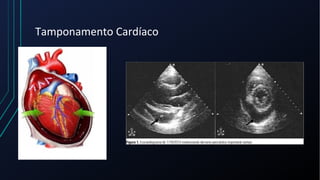

Dor torácica pode ter diversas causas, incluindo cardíacas como síndrome coronariana aguda, dissecção de aorta e pericardite, e não cardíacas como problemas pulmonares, musculoesqueléticos e do trato gastrointestinal. É importante avaliar a história clínica, características da dor e exame físico para identificar a possível causa e orientar o tratamento adequado.